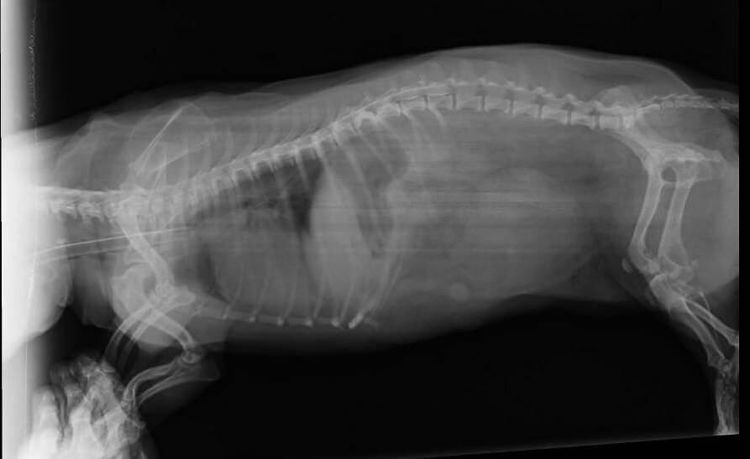

- Radiographie de la colonne vertébrale. Cet examen permettra de déterminer la zone touchée et l'étendue des lésions des tissus vertébraux et des disques intervertébraux. Les radiographies sont essentielles au diagnostic de la discopathie.

Les méthodes diagnostiques les plus informatives sont l'imagerie par résonance magnétique et la tomodensitométrie. Cependant, ces examens sont rarement pratiqués sur les animaux en raison de leur coût.